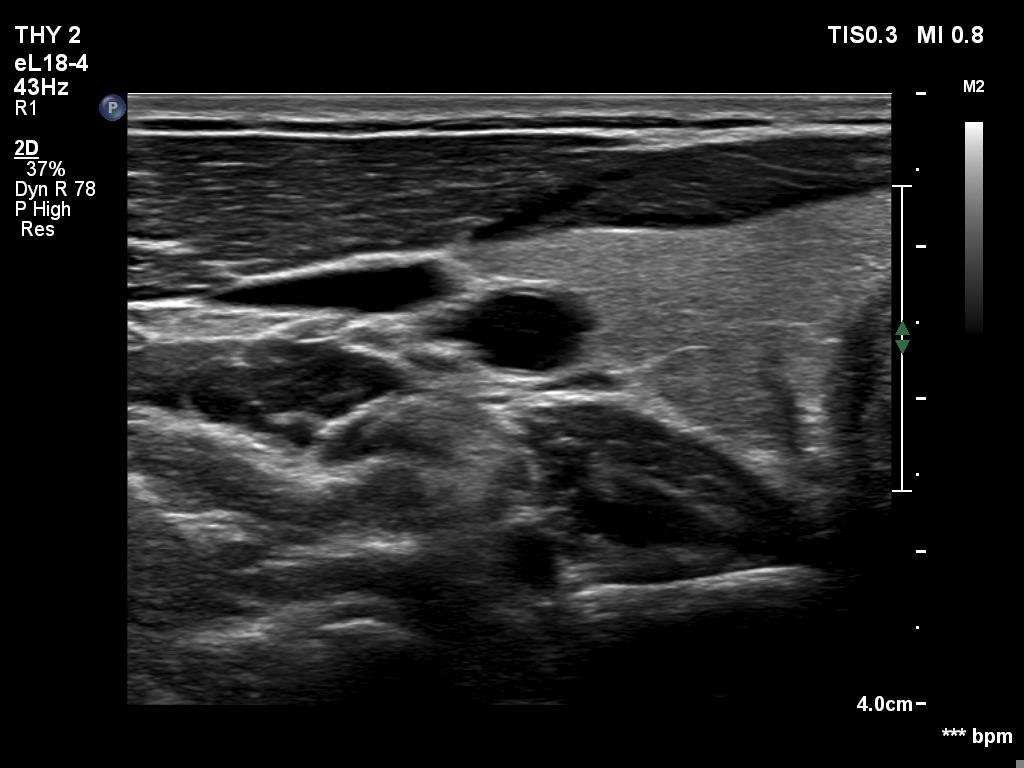

Ultrasonography. The thyroid was echonormal. There was a discrete, minimally hypoechoic area in the dorsal part of the right lobe. This was a technical artifact, caused by a connective tissue band crossing the thyroid. Although on transverse scan, the lesion looked deceptively as a discrete lesion, the real situation became clear on longitudinal scan.

The area in question did not correspond to a discrete lesion. It seemed to be circumscribed because of the presence of connective tissue running ventral which hindered the penetrance of ultrasound wave, therefore made the dorsal area hypoechoic.